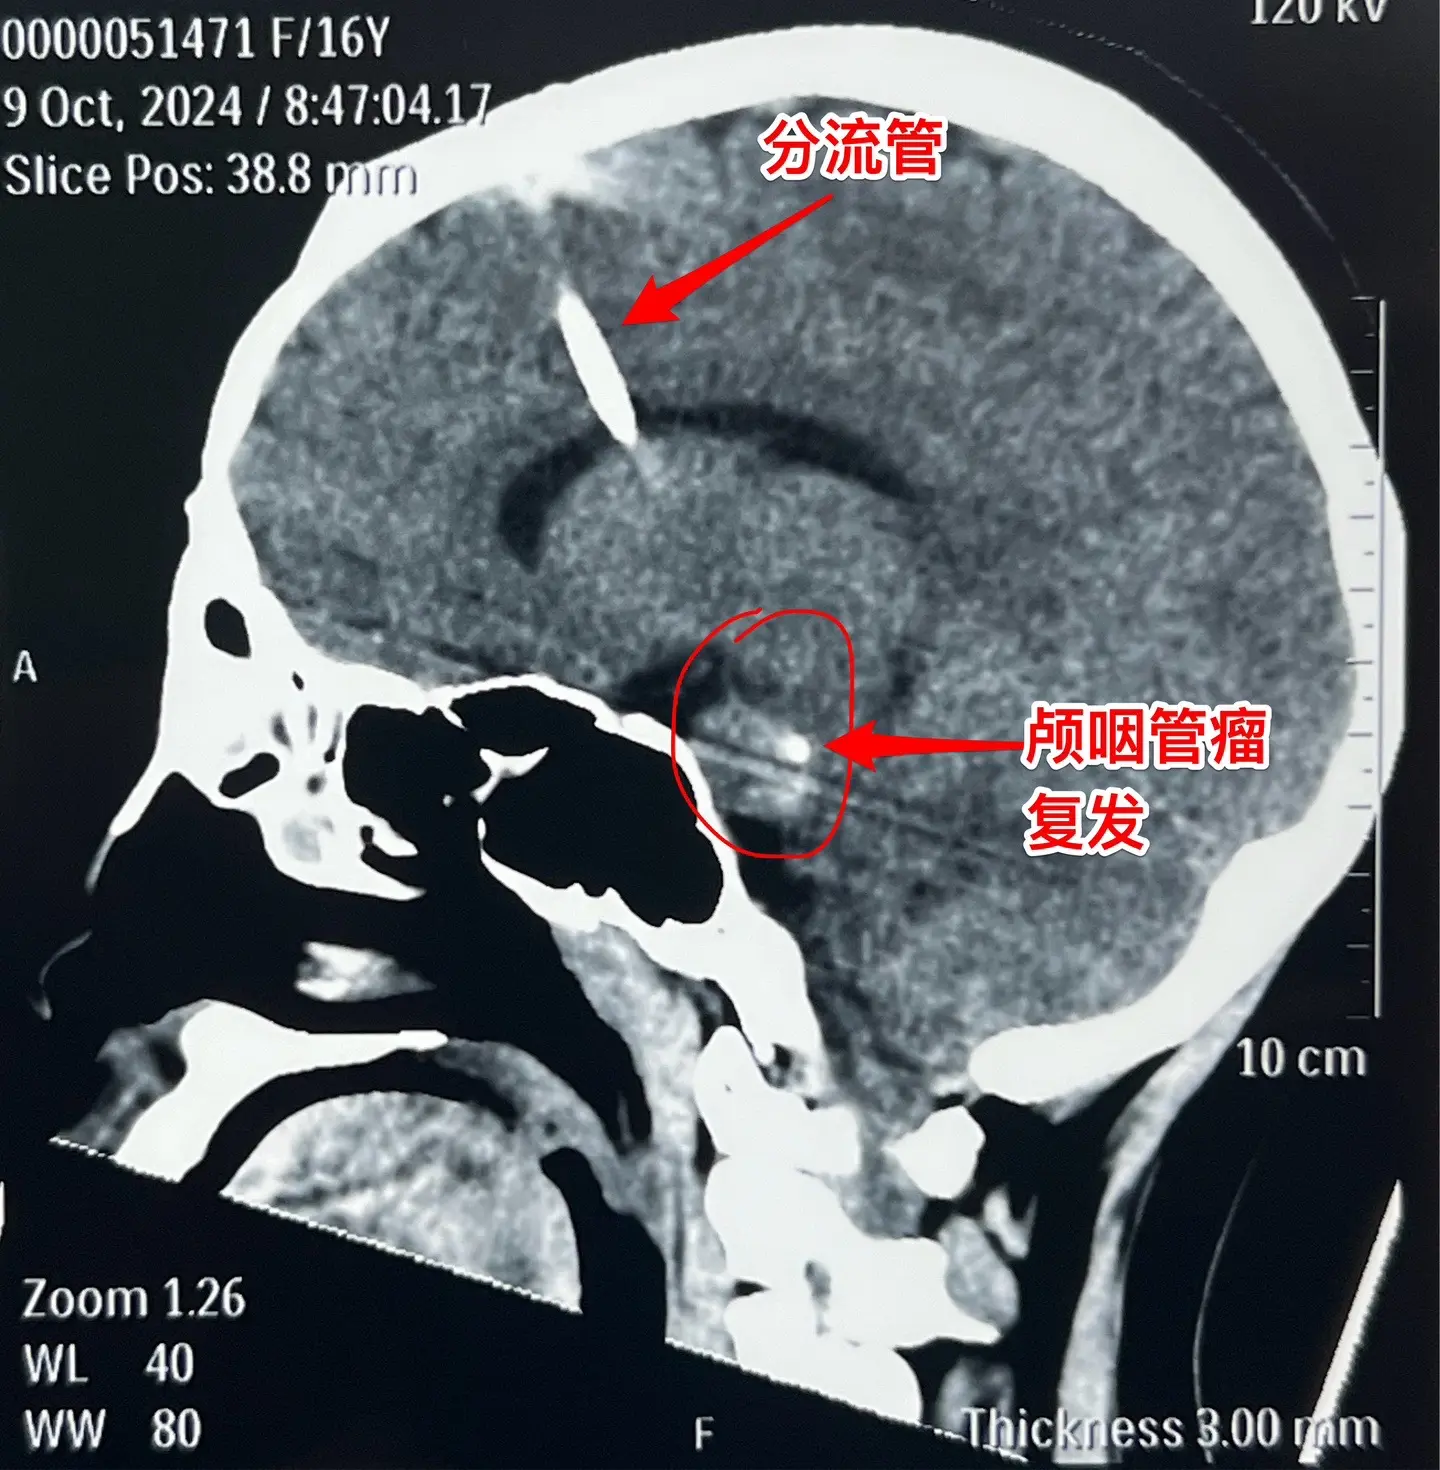

3次复发的颅咽管瘤也要积极治疗。16岁杭州女生,因颅咽管瘤于10年前在外院行开颅手术。8年前发现颅咽管瘤复发(在右侧额叶-鞍区)在我科作了手术,随后多年复查磁共振,7年内均未见肿瘤复发。本以为她的颅咽管瘤已经得到治愈,不曾想八个月前行磁共振检查发现肿瘤有复发迹象,体积很小,观察八个月常规复查磁共振发现肿瘤体积增大了许多,见图,肿瘤起源于左侧桥脑-中脑表面,和普通的颅咽管瘤位置不同。 10月11日作了手术,将这个复发肿瘤彻底切除了。手术后女孩子恢复很顺利,希望经过三次手术后肿瘤不再复发。